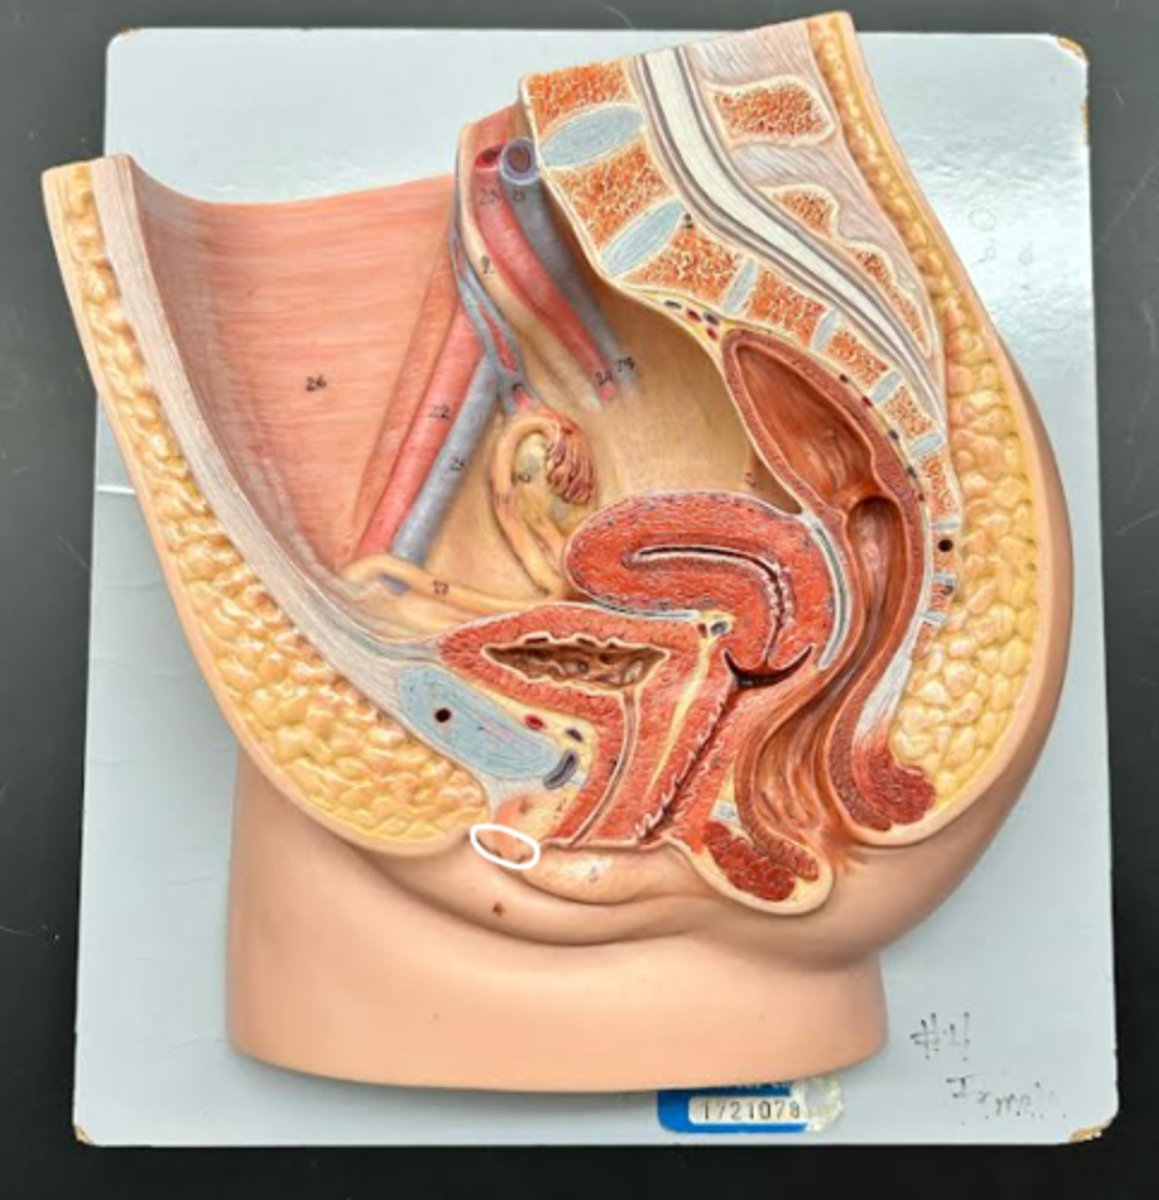

Chapter 29 Anat Phys: Female Reproductive System

Vagina

Vaginal orifice

Hymen

Vaginal fornix

Ovary

Fallopian tube

Fimbriae

Infundibulum

Ampulla

Isthmus

Uterus

Perimetrium

Myometrium

Endometrium

Fundus

Body of uterus

Cervix

Internal os

Cervical canal

External os

Labia majora

Labia minora

Prepuce

Vestibule

Clitoris

External urethral orifice